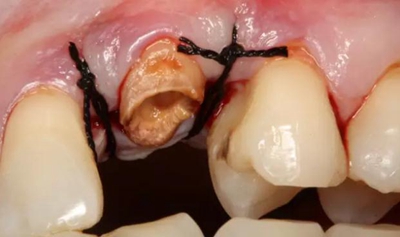

患牙遠中邊緣嵴完整,強度沒有降低,故擬保留遠中邊緣嵴,高嵌體修復。首先去除腐質(zhì)及原墊底材料,流體樹脂+3M Z350XT樹脂墊底。局麻下行冠延長手術。在此需要提及個人的一個觀點。冠延長手術原則上要求3-6個月以上才能永久修復。但是個人喜歡后牙肩臺建立在齦上,所以修復后的修復體邊緣位于牙齦上方1mm,對牙周的愈合影響較?。ㄈ绻麨辇l下邊緣則要慎重),故該患者術中按照齦上邊緣的設計進行冠延長手術。以下為術中:

改良垂直褥式縫合關閉傷口,傷口無明顯滲血,高嵌體預備完畢后,硅橡膠取模,見邊緣清晰。灌注模型,模型上3MZ350XT分層堆塑高嵌體。

一周后拆除縫線,試戴高嵌體,試戴合適后雙固化粘結。調(diào)合,拋光。